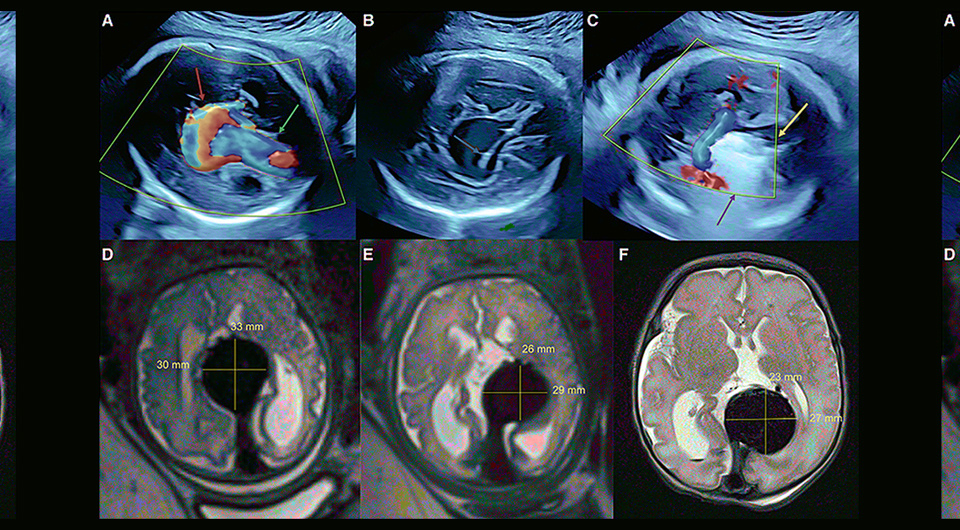

Американские хирурги провели первую в мире внутриутробную операцию по эмболизации артериовенозной мальформации большой мозговой вены — вены Галена. По сообщению, опубликованному в журнале Stroke, ребенок родился недоношенным, однако операция предотвратила тяжелые поражения головного мозга, связанные с пороком, которые могли произойти во время родов или после рождения.

Врожденный порок развития (артериовенозная мальформация) вены Галена (большой мозговой вены) встречается довольно редко — примерно у одного из 25 тысяч новорожденных. При этом такая аномалия имеет крайне неблагоприятный прогноз и ведет к летальному исходу вскоре после рождения. Дело в том, что между близлежащими артериями и веной Галена образуется шунт, по которому в венозное русло поступает много артериальной крови. Во внутриутробном развитии такое патологическое соединение сосудов практически не влияет на жизнедеятельность плода — из-за низкого сопротивления плаценты поток крови из аорты в головной мозг не такой интенсивный.